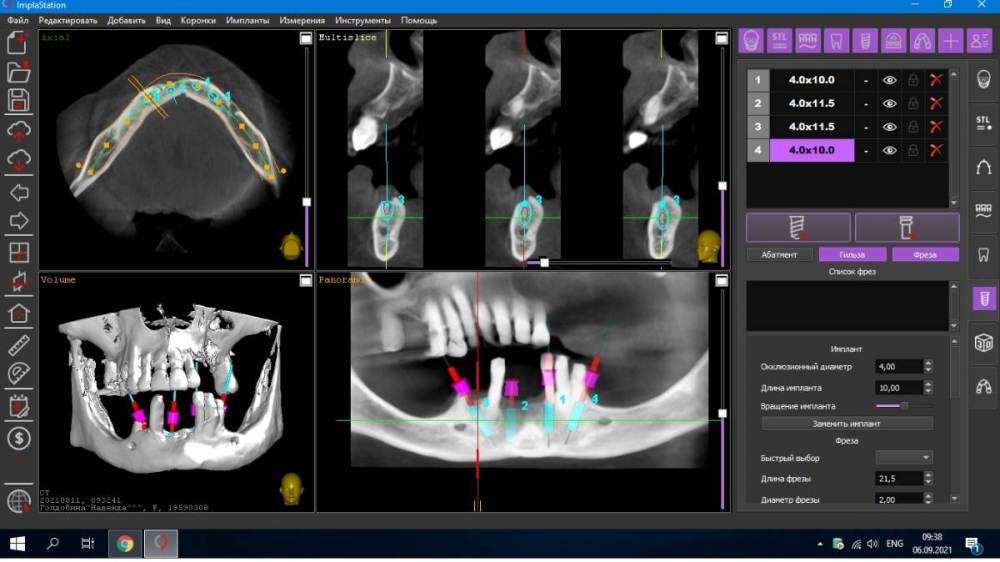

Fatal Опубликовано 6 сентября, 2021 Поделиться Опубликовано 6 сентября, 2021 (изменено) Доброго времени суток коллеги. Есть один клинический случай, где я планирую сделать все на 4, возможно с немедленной нагрузкой. Столкнулся с тем, что foramen mentale четко видно, но ''веточка'' от него выходит еще более медиально особенно в 4 квадранте (фото прилагаю) и тогда не получается поставить имплант в области 44 зуба под углом, что б шахта выходила более дистально для меньшего рычага. (планировалось закончить пятыми зубами или 6ки размоделировать как премоляры). Атрофия значительная в жевательном отделе, костные пластики не планируются. Импланты на фото расставлены примерно, для понимания картины. Вопрос: как ставить имплант в области 44 зуба, если '' веточка'' ментале выходит еще более медиально, также с зоной безопасности в 2 мм? (тогда я упрусь в имплант в области 41-42) -- 4 фото, обведено красным Изменено 6 сентября, 2021 пользователем Fatal Ссылка на комментарий

maksimstom Опубликовано 7 сентября, 2021 Поделиться Опубликовано 7 сентября, 2021 Примерно как нарисовали, так и ставить, эти резцовые ветки вроде как на беззубой челюсти не важны. И импл можно подлиннее взять , чтобы насквозь пройти канал Ссылка на комментарий

Александр07 Опубликовано 10 сентября, 2021 Поделиться Опубликовано 10 сентября, 2021 Ветку честно говоря не увидел, я бы больше наклонил имплантат, и длиннее, платформу импл максимально над менталисом расположить нужно постараться , это наиболее дистальное возможное положение Ссылка на комментарий